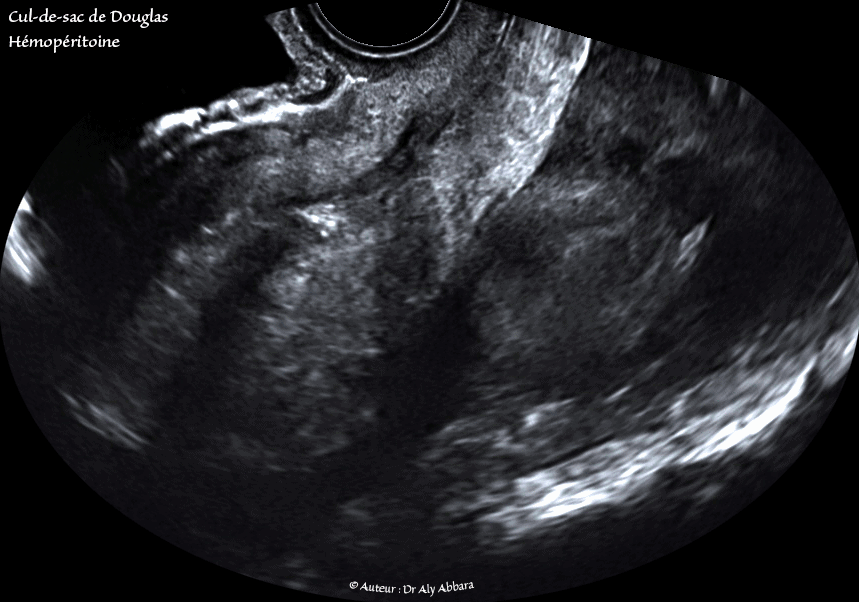

Hémopéritoine inondant le petit pelvis

• Images échographiques animées montrant un hémopéritoine inondant la cavité abdominale ; il est visible sur ces images au niveau du petit pelvis et au niveau de l'espace de Morison.

• En per-opératoire cette hémorragie intra-abdominale est estimée à 1 300 ml du sang ; elle est provoquée par une grossesse extra-utérine tubaire distale évolutive âgée de 9 SA et 2 jours en cours d'expulsion par un avortement tubo-abdominal.